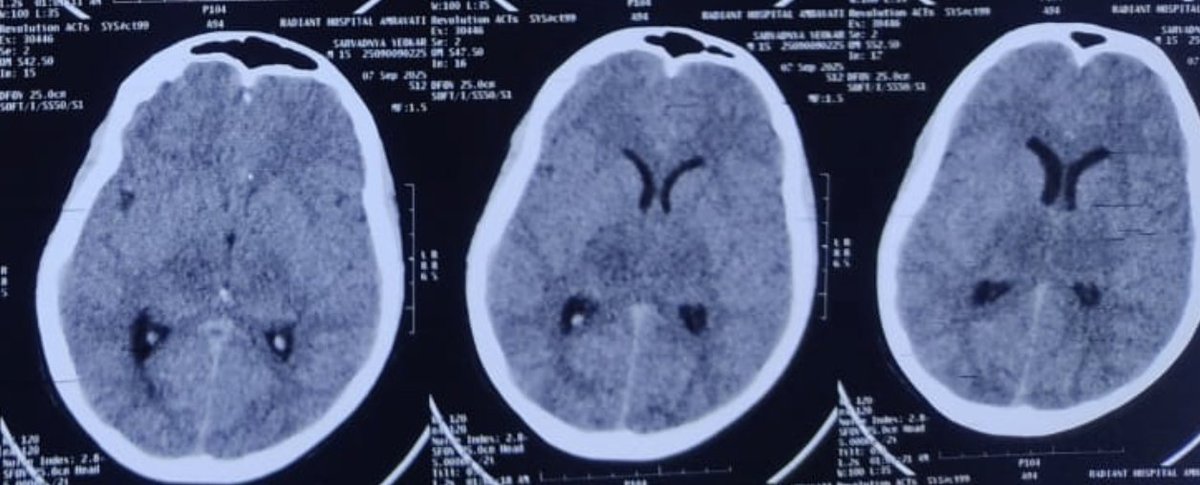

15-year-old boy 4 days of fever → seizures → unconscious CT scan: bilateral thalamic hypodensities. Not your routine viral encephalitis. This is where you must think of Acute Necrotizing Encephalopathy (ANE) — a para-infectious cytokine storm that needs early steroids &

11

35

227